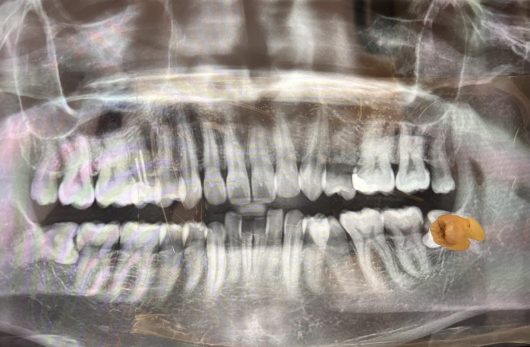

Preparation for oral surgery involves several steps: first, undergo a detailed dental examination with X-rays to assess the condition of your teeth and jaw.

Oral surgery for wisdom tooth extraction is a procedure to remove one or more wisdom teeth — the four permanent adult teeth located at the back corners of your mouth.

This surgery is necessary when wisdom teeth are impacted, causing pain, infection, or other dental problems. The process involves making an incision in the gum tissue to expose the tooth and bone, removing bone that blocks access to the tooth root, and then extracting the tooth.